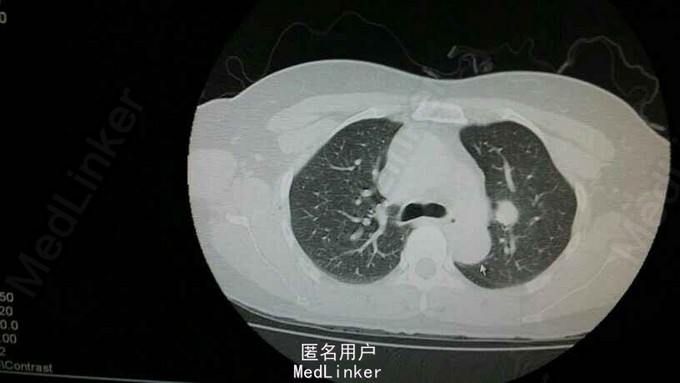

肺部阴影(肺癌? 真菌感染?)-医联

680x383 - 39KB - JPEG